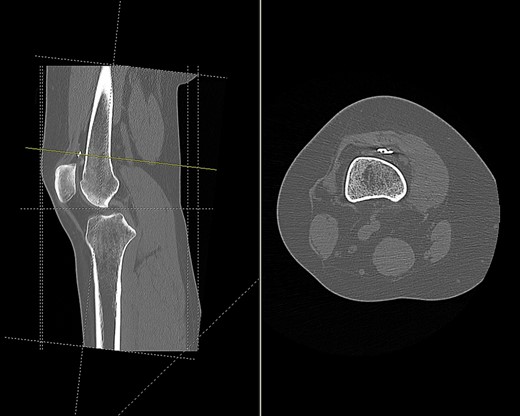

Imaging enabled assessment of the graft tunnels (Figs 2 and 3). It appeared that an oblique tunnel had been drilled from the medial epicondyle to the anterior cortex of the femur at the level of the suprapatellar fat pad.

CT scan of the right knee showing entry point and oblique path of femoral tunnel at medial epicondyle (sagittal and axial view).